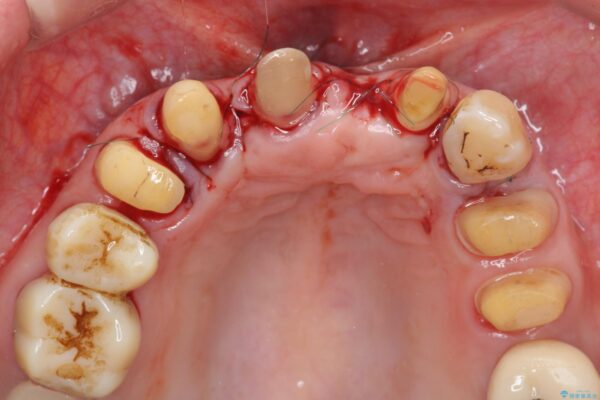

治療中

歯の総合的なマネージメントを行う包括的歯科治療の実践[ 歯周病・矯正・セラミック補綴 ] 治療中画像 歯の総合的なマネージメントを行う包括的歯科治療の実践[ 歯周病・矯正・セラミック補綴 ] 治療中画像 歯の総合的なマネージメントを行う包括的歯科治療の実践[ 歯周病・矯正・セラミック補綴 ] 治療中画像 歯の総合的なマネージメントを行う包括的歯科治療の実践[ 歯周病・矯正・セラミック補綴 ] 治療中画像 歯の総合的なマネージメントを行う包括的歯科治療の実践[ 歯周病・矯正・セラミック補綴 ] 治療中画像 歯の総合的なマネージメントを行う包括的歯科治療の実践[ 歯周病・矯正・セラミック補綴 ] 治療中画像 歯の総合的なマネージメントを行う包括的歯科治療の実践[ 歯周病・矯正・セラミック補綴 ] 治療中画像 歯の総合的なマネージメントを行う包括的歯科治療の実践[ 歯周病・矯正・セラミック補綴 ] 治療中画像 歯の総合的なマネージメントを行う包括的歯科治療の実践[ 歯周病・矯正・セラミック補綴 ] 治療中画像 歯の総合的なマネージメントを行う包括的歯科治療の実践[ 歯周病・矯正・セラミック補綴 ] 治療中画像 歯の総合的なマネージメントを行う包括的歯科治療の実践[ 歯周病・矯正・セラミック補綴 ] 治療中画像